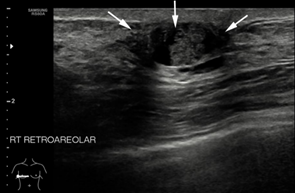

A 72 years old gentleman presented to our centre in 2019 with the right breast swelling and painless nipple bloody discharge for the past three months. He claimed the swelling was progressively increasing in size with changes noted on the surface of the nipple skin. The patient also had constitutional symptoms such as loss of weight and loss of appetite for the past one year. He claimed he lost about 10kgs in the last 6 months. Otherwise, the patient denies having any family history of breast cancer nor consumed any kinds of hormonal pills or supplements. Triple assessment was done on the patient and clinical examination revealed a hard, non-tender lump at the retro areolar region measuring about (2x1) cm. There were blood and serous discharge from the nipple. No mass was palpable on the other region of the breast or contralateral side. Bilateral axillary lymph nodes were not palpable. Initial right breast ultrasound noted the presence of cystic and solid lump at the retro areolar region measuring (1x1x1.8) cm. Also noted was internal vascularity with a layer of sediment within the cystic mass. The imaging findings were categorized as BIRADS 4.We then proceed with computed tomography (CT) scan and noted the presence of a focal enhancing retro areolar lesion on the right breast measuring (0.8x0.8x1.0) cm with no extension to the underlying structures. There were some sub-centimetres bilateral axillary lymph nodes with preserved fatty hilum with largest was 0.9cm in the right axilla. Ultrasound-guided biopsy was performed and was confirmed to be of intra-ductal papillary carcinoma in origin. The patient was staged as T1N0M1 according to the TNM classification. The patient was arranged for a right mastectomy the following week. He was then discharged home well after a week and a surveillance mammogram was performed a year later and no focal lesion seen on the left breast (Figure 1 & 2).

Figure 1 Ultrasound image of the right breast showing a mixed solid cystic lesion with microlobulated border at the retro-areolar region.

Figure 2 CT scan image axial view showing a focal enhancing lesion at the right retro-areolar region with no extension to the underlying pectoralis major muscle.